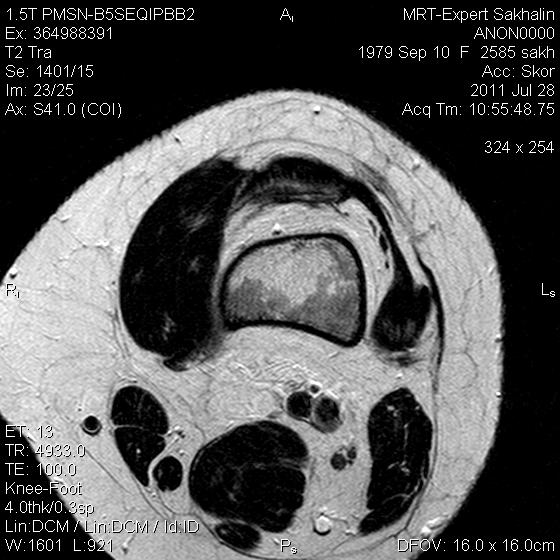

Коленный сустав

Подглядела случай у коллеги.

Что это может быть?

Не вижу криминала. А на что жалуется девушка?

P.S. В костях - это, скорее всего, резидуальный красный костный мозг.

Жалоба у всех одна на всех-болит.

участки гемопоэтического костного мозга